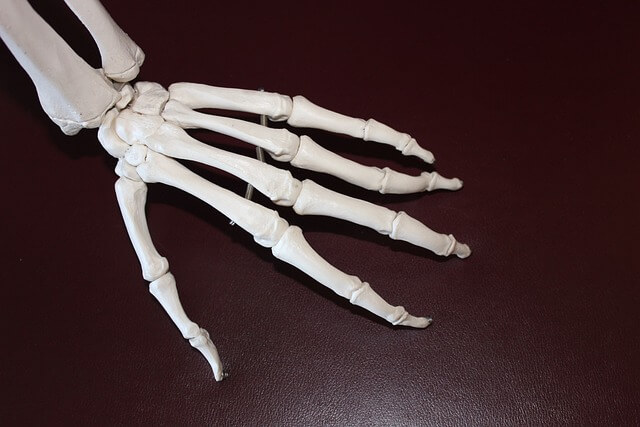

손가락 관절염, 손가락 관절 통증, 손가락 염증, 엄지 손가락 마디 통증, 손마디 통증, 손가락터널증후군 등 여러 가지 문제들이 손가락의 움직임을 제한하고 일상생활에 큰 불편을 초래합니다.

퇴행성 손가락 관절염은 손가락 끝마디에 주로 발생하며, 연골이 닳아 염증이 생기는 질환입니다.

관절염은 관절의 염증을 일으켜 통증과 부기를 초래하며, 손가락 끝마디가 굵어지고 돌출되는 특징이 있습니다.

3. 방아쇠수지 증후군(Trigger Finger)

방아쇠수지(건초염)는 손가락 마디 통증의 중요한 원인 중 하나입니다.

힘줄을 싸고 있는 활액막에 염증이 생기는 질환으로, 손가락을 구부리고 펴는 데 문제가 생깁니다.

손가락을 움직일 때 통증이나 딸깍거리는 소리인 탄발음이 발생하며, 종물이 만져지기도 합니다.